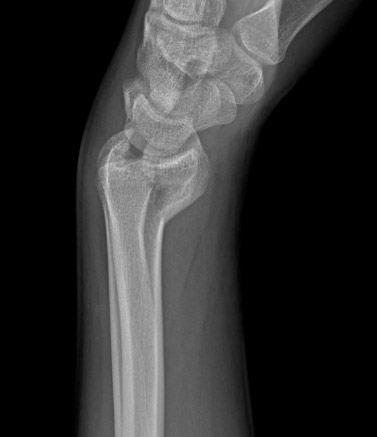

Fratura intra-articular do tipo B (simples) do rádio distal: vista lateral

Do acervo do Dr. Chaitanya S. Mudgal